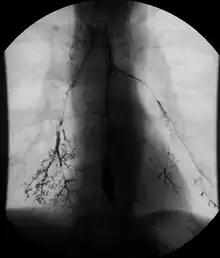

Normal barium swallow fluoroscopic image, showing the ingested barium sulfate being induced down the oesophagus by peristalsis.